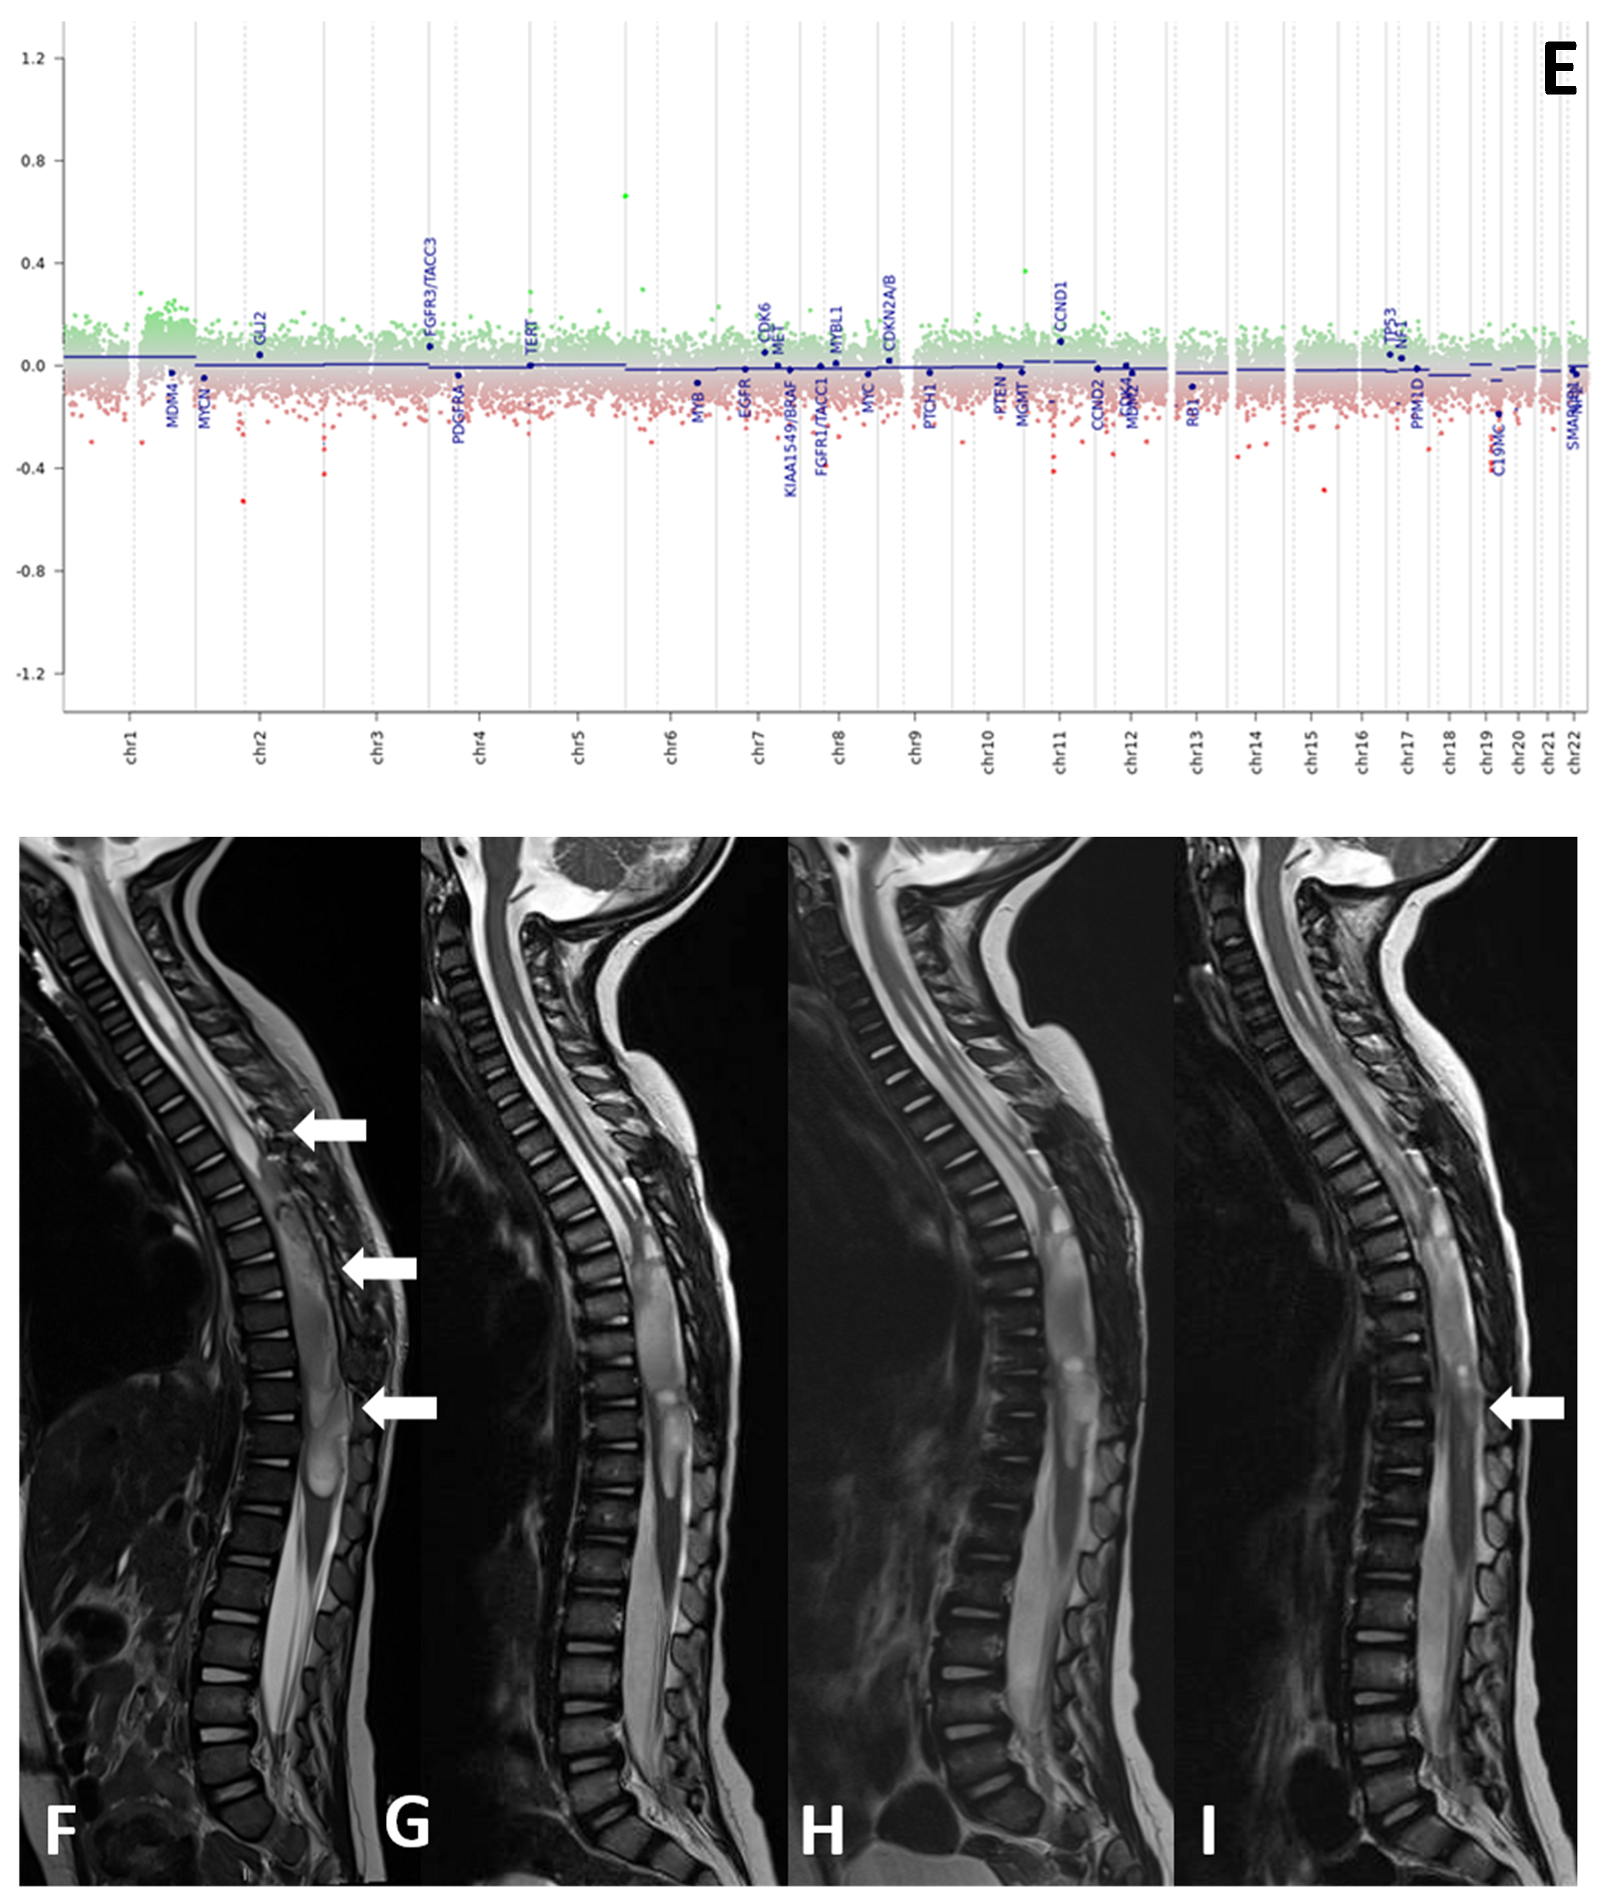

Histological samples, molecular profiles, and MRI imaging of this patient are reported in Figure 1.

(A–I) Histological samples (A–D), molecular profile (E), and MRI imaging at diagnosis (F), after standard chemotherapy regimens (G) and at three months (H) and six months (I) after the start of larotrectnib in patient number 7. The tumor consisted of small spindle cells embedded in a myxoid background (A). Mitoses were present throughout. The tumor showed foci of necrosis (B) and microvascular proliferation. OLIG2 was diffusely expressed (C); GFAP expression was multifocal (D). Molecular profiling with classifier v11.b4 did not reveal any match. Revaluation with classifier v12.3 showed GBM pedRTK1a glioblastoma, pediatric RTK1 type, subtype A (score 0.31337). At imaging evaluation, the neoplasm is characterized by solid-cystic aspect. Sagittal T2-weighted sequences at four consecutive time points: post first surgery approach (arrows, (F)), after induction chemotherapy (G), after three months (H) and after six months after the start of larotrectnib (I). At the last follow-up, there was a moderate reduction in the size of the neoplasm, especially in the solid caudal portions (arrow, (I)).

Two patients in our cohort received larotrectinib after completing first line chemotherapy: in one case, larotrectinib was administered after radiological and clinical evidence of progressive disease and induced an impressive complete remission at the 2-year follow-up, without severe side effects or impact on neurological development; the second patient, with refractory disease after induction, received the NTRK-inhibitor with a very good partial response documented in MRI studies at four and six months after starting larotrectinib (Figure 1).